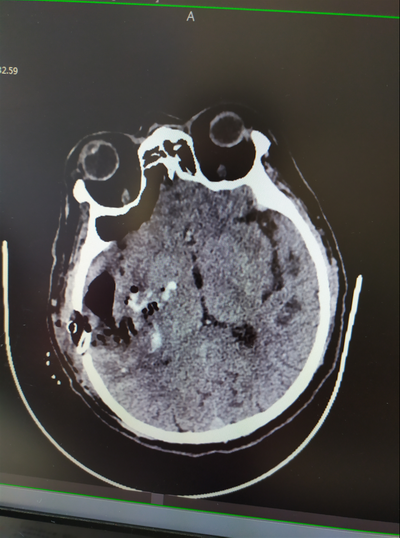

術(shù)后CT顯示

該患者幕上出血,出血量>20ML,有急診手術(shù)指征。出血位于右側(cè)非優(yōu)勢半球,血腫距皮層最近處不到1cm。外一科團隊經(jīng)過認真討論,為患者制定了個體化的治療方案,在腦出血早期為患者進行了手術(shù),選擇右側(cè)經(jīng)顳部直切口,打開大小約3×3cm小骨窗,選擇相對功能“啞區(qū)”,經(jīng)右側(cè)顳中回造瘺,神經(jīng)內(nèi)鏡直視下清除血腫、止血。術(shù)后患者神志清楚,目前在進一步康復中。